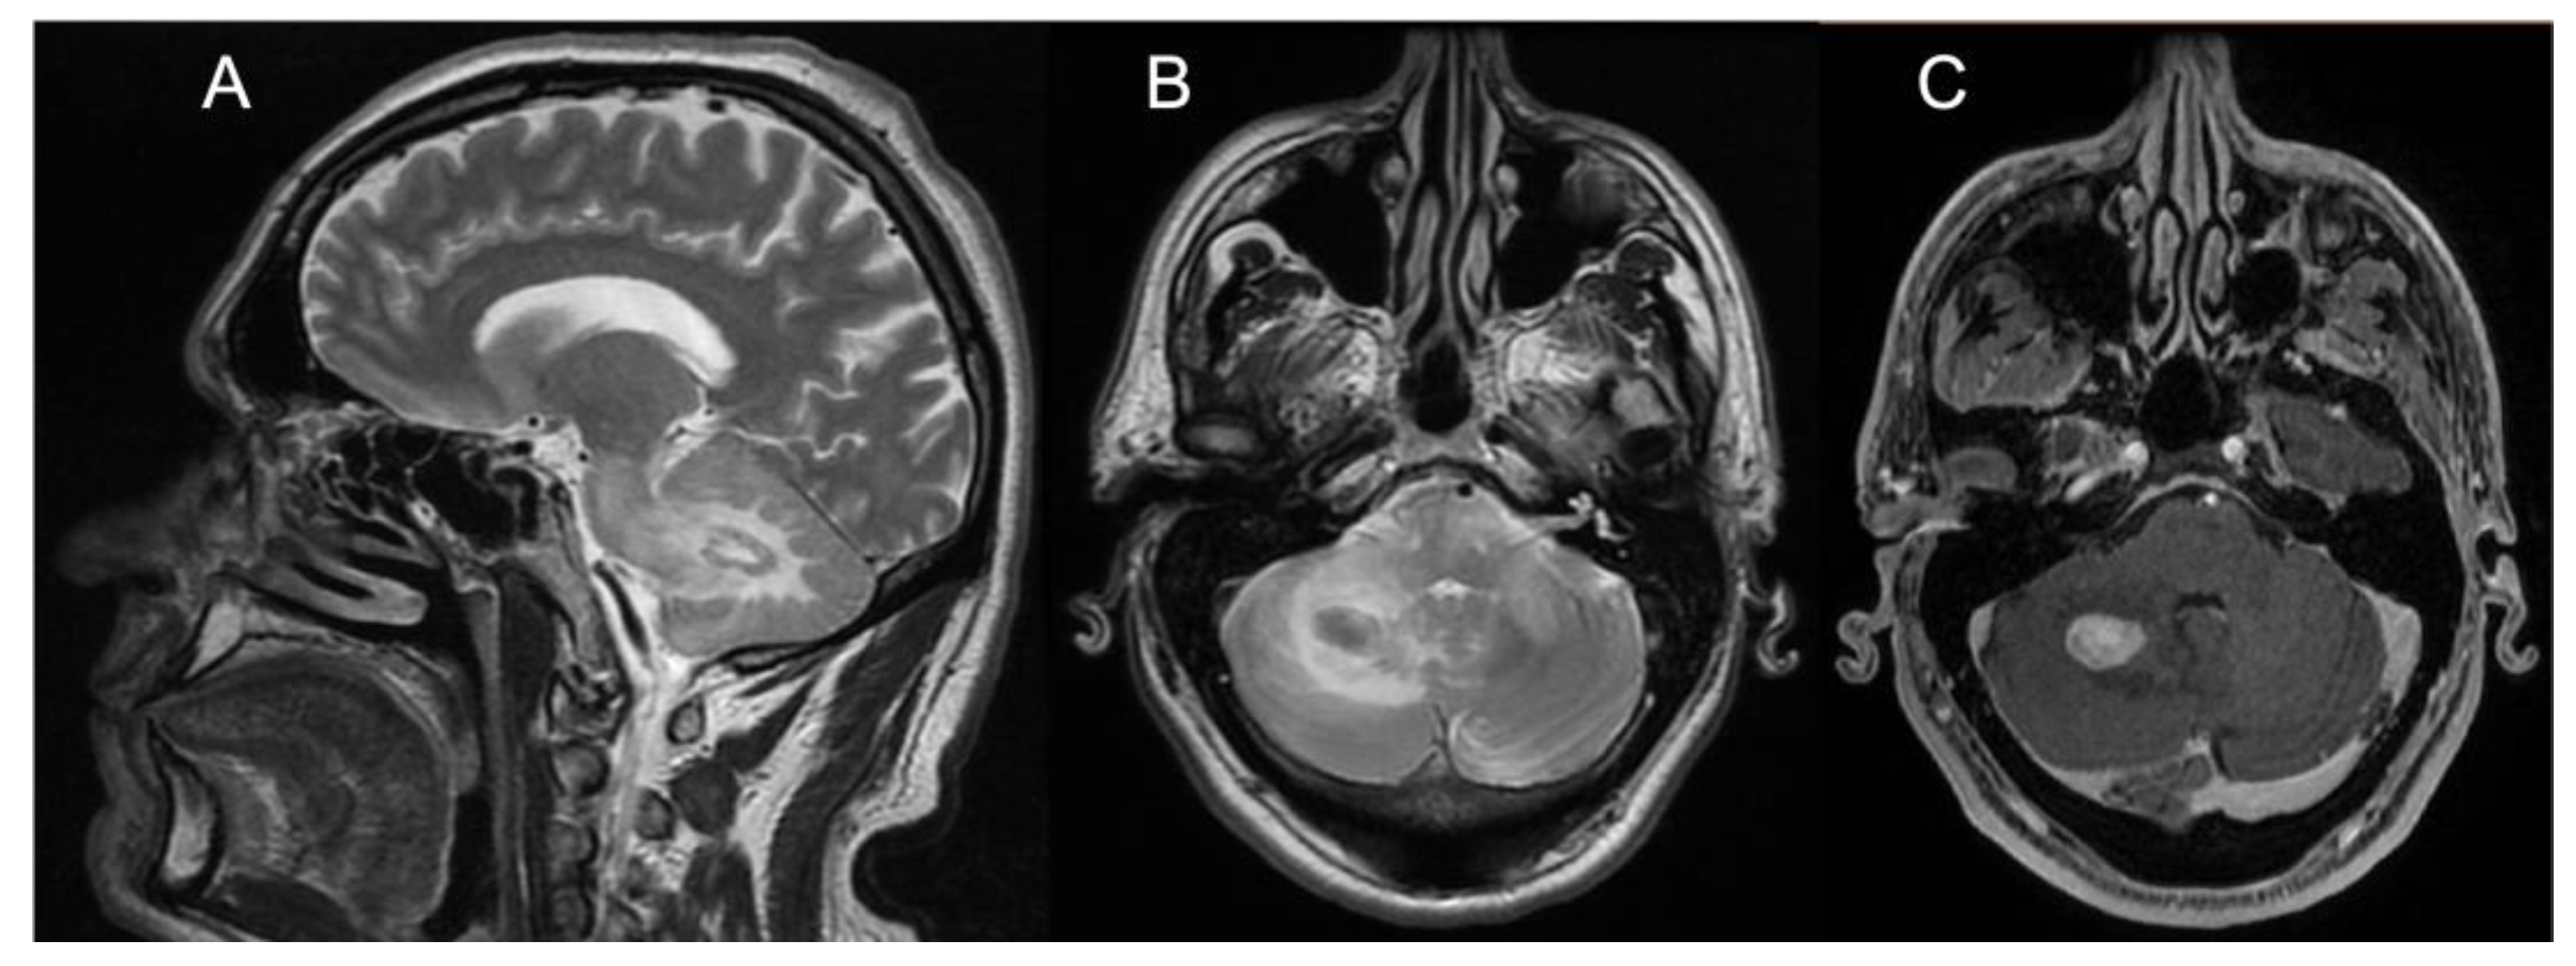

Brain MRI showed T2/FLAIR hyperintense signal alterations without contrast enhancement variably involving the white matter of cerebellar hemispheres, middle cerebellar peduncles, dentate nuclei, pons, and midbrain and cerebral peduncles in all cases (Figure 1). Three patients (Pts 1, 2, 4) also presented similar supratentorial T2/FLAIR hyperintensities variably involving the paratrigonal area, posterior arm of the internal capsule, globus pallidus, peri-aqueductal, and parahippocampal areas, with evidence of gadolinium contrast enhancement in the paratrigonal area not shown in Pt 3. Moreover, signs of cerebellar atrophy and bilateral hypointense signal abnormalities in basal ganglia on SWI sequences, suggestive of iron deposition, were evident in Pts 1, 3, and 4 (Figure 1). Of note, in Pt 2 manifesting a subacute neurological outcome, MRI also showed two nodular lesions (30 × 20 × 20 mm3) in the right cerebellar hemisphere with contrast enhancement (Figure 2) and elevated levels of r-CBV (regional cerebral blood volume) on the perfusion study and DWI-restriction, indicative of hypercellularity. Finally, Pt 3, affected by diabetes insipidus, also presented an empty sella. Signs of paranasal sinuses or mastoid inflammation were evident in three patients (Pts 1, 2, and 3). Spinal cord MRI was normal in all patients.

Regarding brain MRI, all our neurological ECD patients had a suggestive “infiltrative pattern”, characterized by T2/FLAIR hyperintense white matter lesions mainly involving the brainstem and the cerebellum, usually without contrast enhancement. Some of them showed similar alterations also in the supratentorial compartment, in one case with focal areas of contrast enhancement. Overall, our data support those of previous reports indicating that the characteristic brain MRI findings in “pure “neurological ECD patients consists of a diffuse, exclusive, or prominent involvement of the infratentorial compartment mainly involving the cerebellum, the brainstem, and the cerebellar peduncles, usually without contrast enhancement [13,14,15,16,21] and with no evidence of meningeal involvement. As an additional diagnostic hint for ECD, diabetes insipidus had occurred in Pt 3 many years before the onset of ataxia. Such a condition is relatively frequent in ECD, being reported in 30–48% of patients, and it may occur, as in our patient, many years before the onset of neurological symptoms. A long-lasting history of diabetes insipidus associated with thickening and contrast enhancement of the pituitary stalk, in the presence of unspecific brain, meningeal, or retro-orbital lesions might also imply a differential diagnosis of IgG4-related disease, sarcoidosis, tuberculosis, or lymphocytic infundibulo-neurohypophysitis. Yet, the association with diffuse signs of long bone involvement is highly suggestive for a diagnosis of neuro-ECD, as discussed shortly after in this section. Finally, two large tumoral nodular lesions in the right cerebellar hemisphere with contrast enhancement were also present in Pt 2, who accordingly manifested rapidly evolving symptoms due to its mass effect in the posterior fossa.

Figure 2. Panel showing brain MRI of Patient #2. (A) Sagittal T2-weighted scan showing one nodular lesion along with extensive hyperintensity of the white matter of the RCH, the ipsilateral MCP, and the pons. (B) Transverse T2-weighted scan (pons level) showing the same nodular hypointense lesion with hyperintensity of the white matter of the RCH, both MCPs and the pons. (C) Transverse T1-weighted scan (pons level) showing marked, homogeneous contrast enhancement of the RCH nodular lesion. Abbreviations: RCH: right cerebellar hemisphere; MCP: middle cerebellar peduncle.